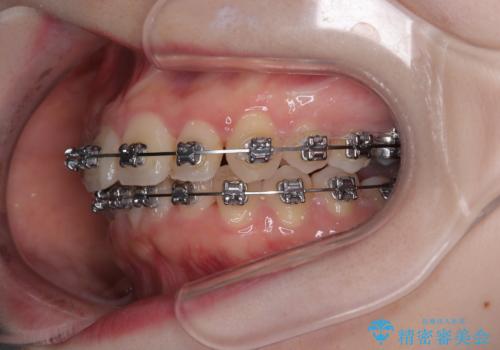

- メタルブラケット

- 1年11ヶ月

- 上下前歯のデコボコを気にして来院された患者様です。

マウスピースでもワイヤー装置でも対応可能でしたが、右側の咬み合わせが上顎がやや前方に位置していることから、補助装置を使用することが推奨されました。

自己管理の煩わしさを気にして、補助装置併用によるワイヤー装置での矯正治療を行うこととしました。

右上と左下の第一大臼歯2本が周辺の歯と比べて位置がずれていたため、ゴムかけやワイヤーに曲げを入れることで移動を試みましたが、どうよら癒着をしており、移動困難と判断されました。

見た目や咬み合わせに違和感がないとのことで、癒着歯の無理な移動は試みずに治療を終えることとしました。